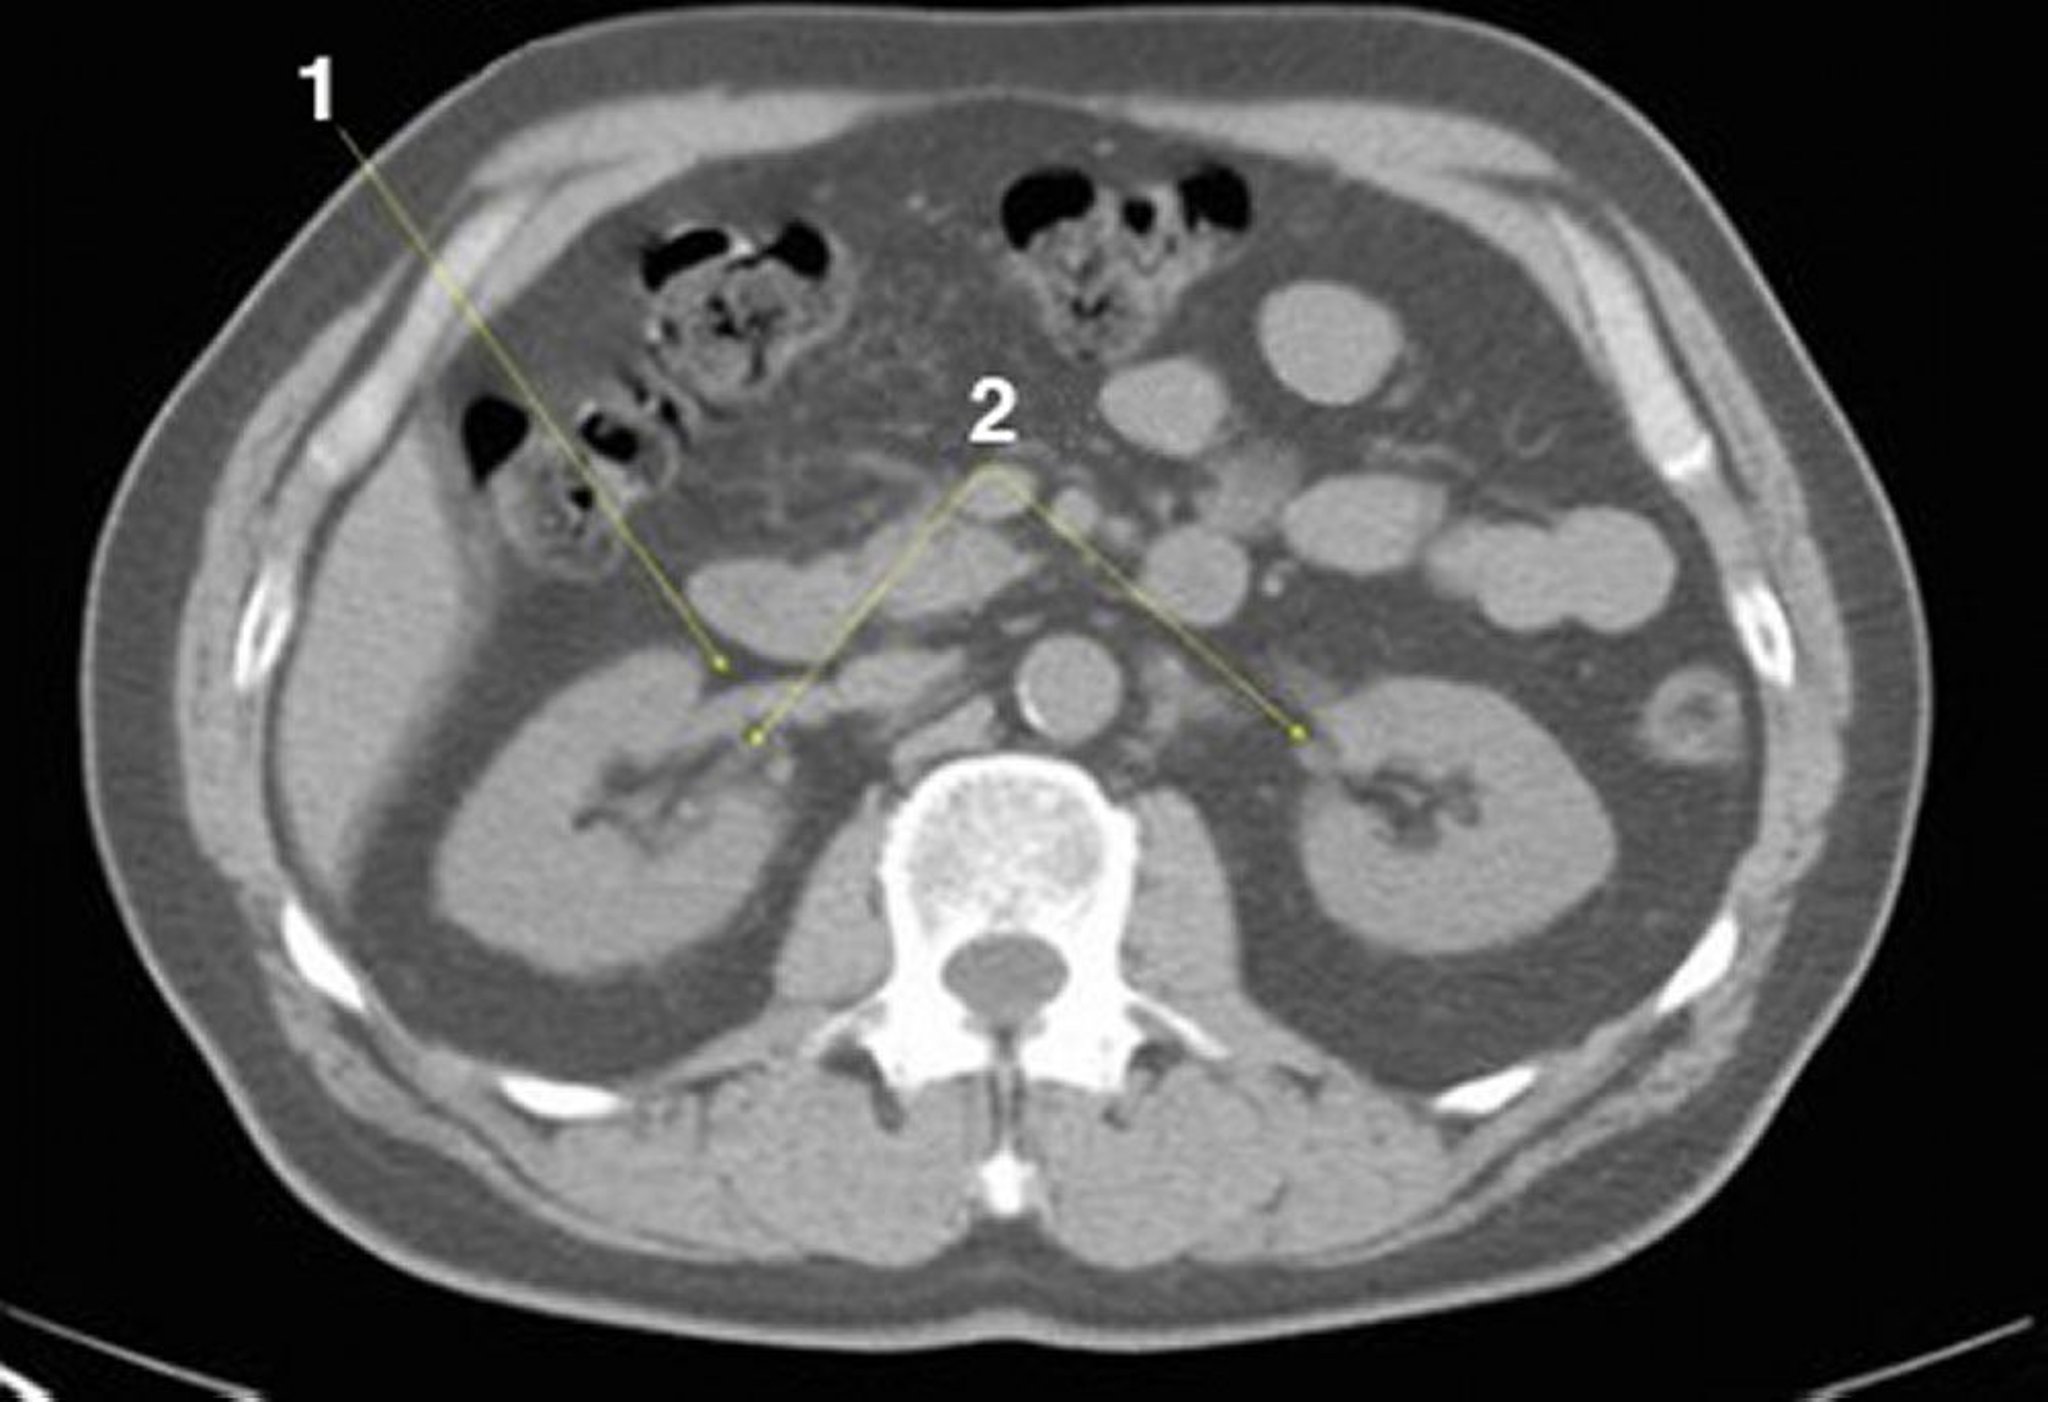

Noncontrast CT Scan of the Abdomen and Pelvis Showing Normal Anatomy (Slide 14)

1 = right renal vein; 2 = kidneys at hila.